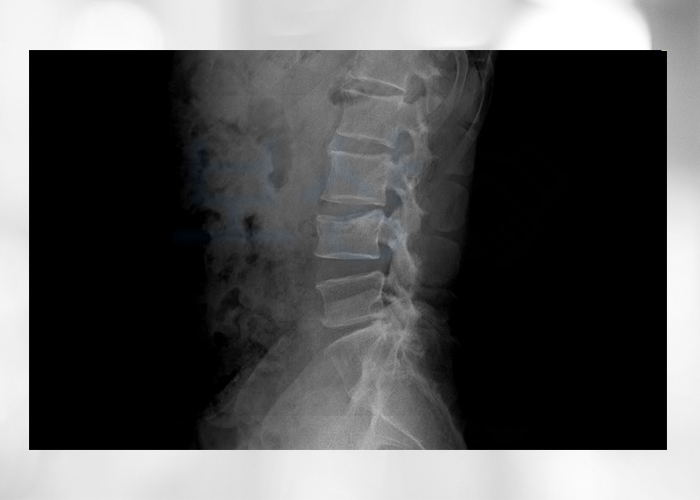

진단명은 "L4 부위의 골절, 폐쇄성 경추의 염좌 및 긴장" 으로서 요추 4번 골절 진단 받으셨습니다

척추 압박골절은 처음 골절되었을 때는 정도가 심해 보이지 않을 수 있지만, 시간이 지나면서 점점 주저앉아 굴절된 부위가 더 명확하게 보이며 따라서 통증이 점점 심해질 수 있습니다 의뢰인 분은 다행히 일찍이 저희 보상파트너에 연락을 주셔서 치료비, 입원비, 골절진단비 외에 후유장해보상에 대해 자세히 설명드릴 수 있었습니다!

척추에 약간의 기형을 남긴 때(15%, 5급) 영구장애

소견을 받게 되었습니다.